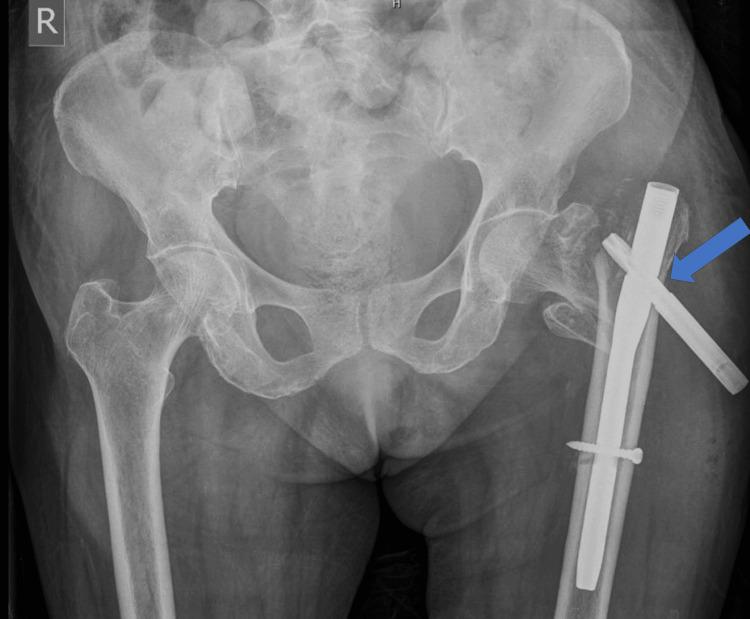

采用带股骨距柄的双极半髋关节置换术治疗老年不稳定型股骨转子间骨折中股骨近端抗旋髓内钉-亚洲型(PFNA2)失败病例

Intertrochanteric (IT) femur fractures in the elderly population comprise a major part of geriatric trauma and fractures. There are various modalities of surgical management, ranging from intramedullary fixation and extramedullary fixation to even replacing the hip joint. Apart from the surgeon's choice, other factors, such as geriatric age, bone quality and osteoporosis, medical comorbidities, life expectancy, pre-operative ambulatory status, muscle strength, type and pattern of fracture, and mental health of the patient, play vital roles in determining the ideal modality of management and the long-term outcome. The present case is a 75-year-old lady who had an IT fracture due to a domestic fall, managed surgically with a proximal femoral nail anti-rotation Asia (PFNA2) for an unstable fracture. She presented with blade back-out on the 11th day postoperatively. The patient was investigated thoroughly, and infection was ruled out. She was managed by the removal of the nail, followed by a cemented calcar-replacing bipolar hemiarthroplasty for an unstable comminuted IT fracture. The patient was ambulatory with a walker by the seventh postoperative day and without a walker by the sixth week, and she was self-sufficient in her activities of daily living. Every geriatric IT fracture must be evaluated thoroughly for contributing factors, such as osteoporosis and fracture pattern, to predict outcomes, and a tailor-made strategy of surgical management and stepwise physiotherapy must be provided to the patient for the best results.

老年人群中的股骨粗隆间骨折是老年创伤和骨折的主要组成部分。手术治疗方式多种多样,从髓内固定、髓外固定到甚至髋关节置换。除了外科医生的选择外,其他因素,如老年年龄、骨质质量和骨质疏松症、合并症、预期寿命、术前活动状态、肌肉力量、骨折类型和形态以及患者的心理健康,在确定理想的治疗方式和长期预后方面起着至关重要的作用。本病例是一位75岁的女性,因在家中跌倒导致股骨粗隆间骨折,对于不稳定骨折采用股骨近端抗旋髓内钉亚洲版(PFNA2)进行手术治疗。她在术后第11天出现刀片退出。对患者进行了全面检查,排除了感染。通过取出髓内钉对其进行治疗,随后针对不稳定的粉碎性股骨粗隆间骨折进行了骨水泥型股骨距替代双极半髋关节置换术。患者术后第7天借助助行器可行走,术后第6周无需助行器,并且在日常生活活动中能够自理。每一例老年股骨粗隆间骨折都必须对骨质疏松症和骨折形态等促成因素进行全面评估,以预测预后,并且必须为患者提供量身定制的手术治疗策略和逐步的物理治疗,以获得最佳效果。